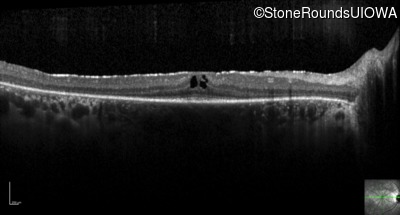

Optical Coherence Tomography - Right -

20/20 -1

Exemplar / OCT Stack

Optical Coherence Tomography - Left -

20/20